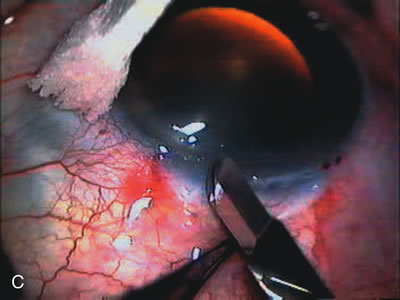

Fig. 7. Phacotrabeculectomy adjacent to a failed filter in cataractous eye. The ability to combine small-incision cataract extraction with trabeculectomy all through the same incision adjacent to the failed filter allows the surgeon to work in a familiar superior area. Avoiding incisions into the existing bleb decreases conjunctival buttonholes, hypotony, operating room time, and subconjunctival bleeding. A. Appearance of failed bleb with exposure of superior temporal quadrant gained with a corneal traction suture. B. Prepare a limbus-based conjunctival flap and a scleral flap. C. This bleb is at high risk to fail again justifying the need for MMC, 0.2 mg/cc applied on a pledget for 4 minutes. D. Insert the keratome and perform phacotrabeculectomy in the usual fashion.